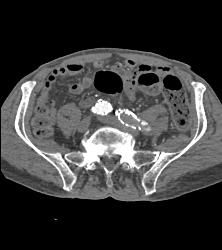

Occluded Left Iliac Artery With A Fem-fem Bypass